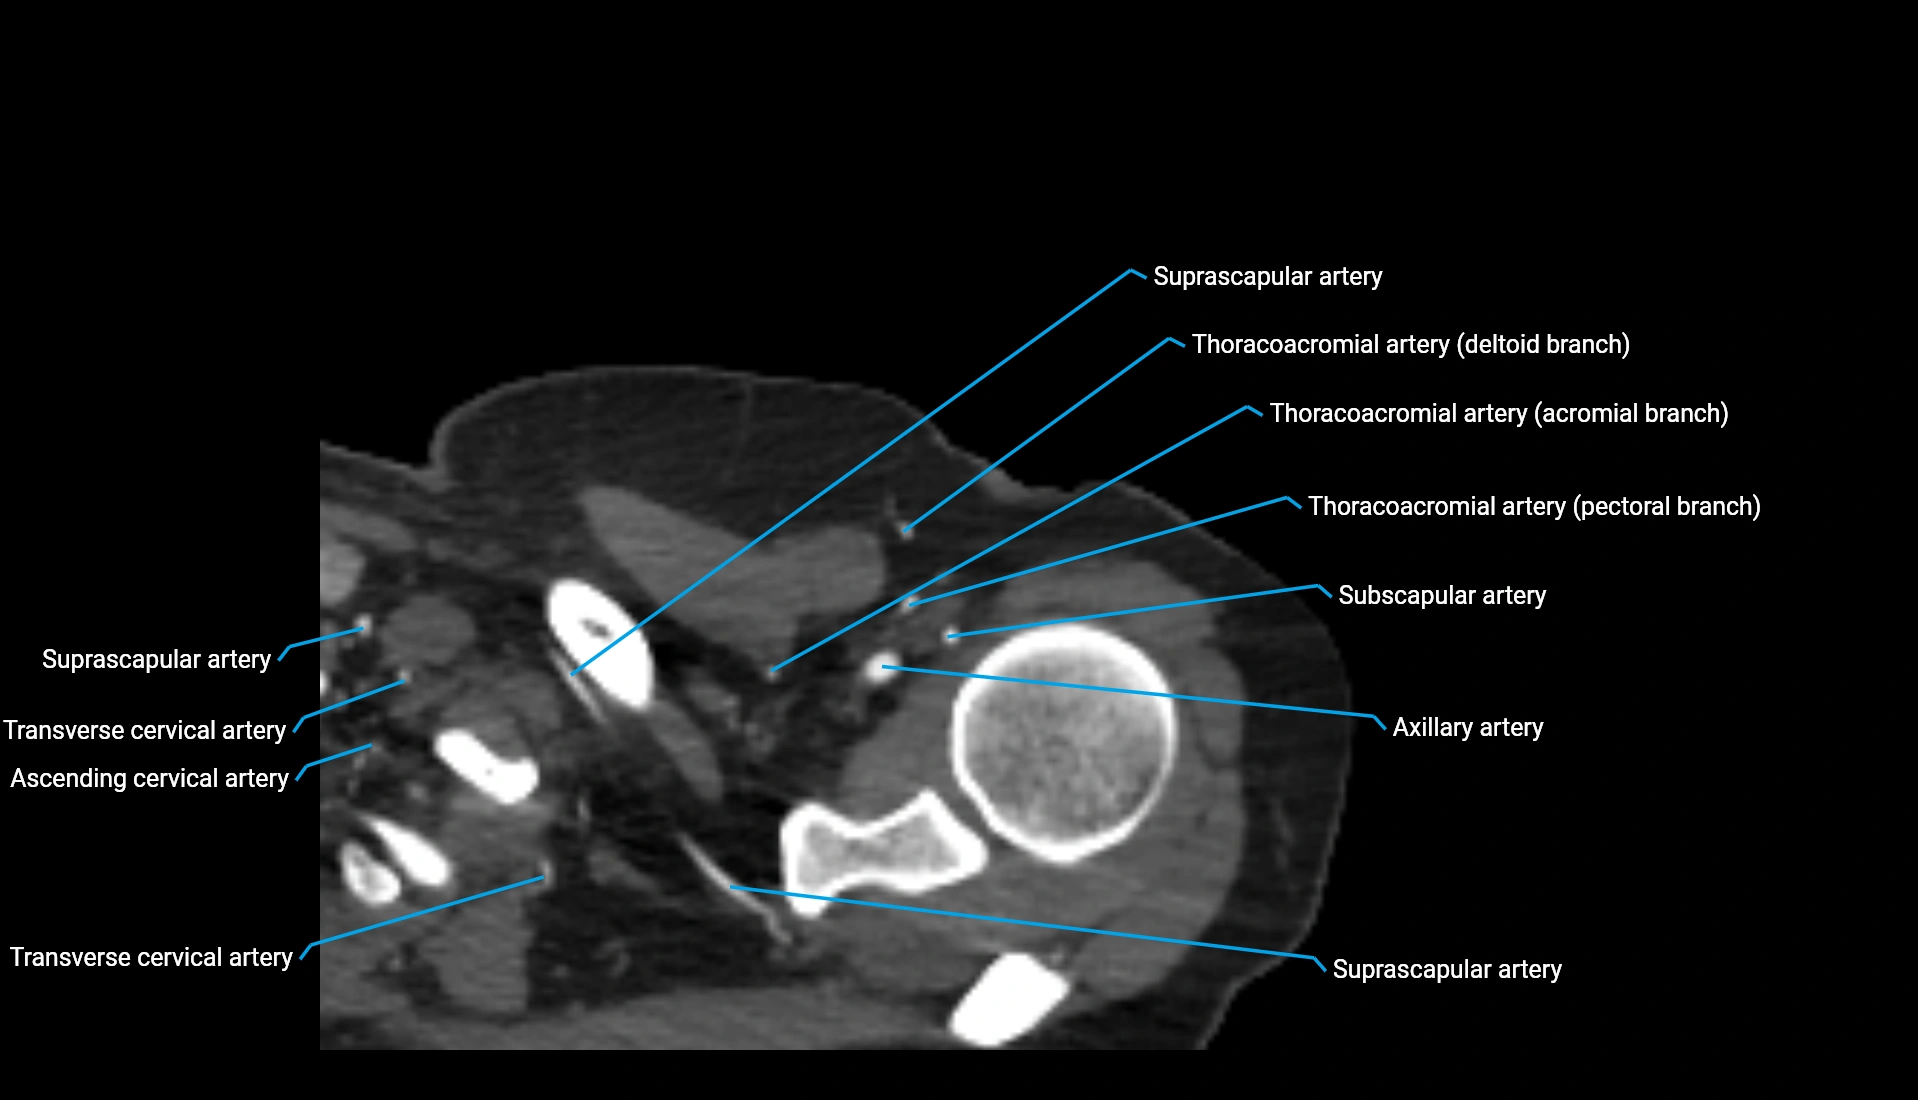

CT Appearance

Non-Contrast CT:

• Cortex: High-density, sharply defined

• Subchondral bone: Dense cancellous matrix

• Articular surface: Smooth concave contour articulating with the capitellum

• Excellent for evaluating bone integrity, alignment, and subtle fractures

Post-Contrast CT:

• Bone: No enhancement

• Joint capsule and synovium: Mild enhancement outlining the joint

• Improves contrast between soft tissues and bony margins

• Useful in detecting subtle joint abnormalities or postoperative changes